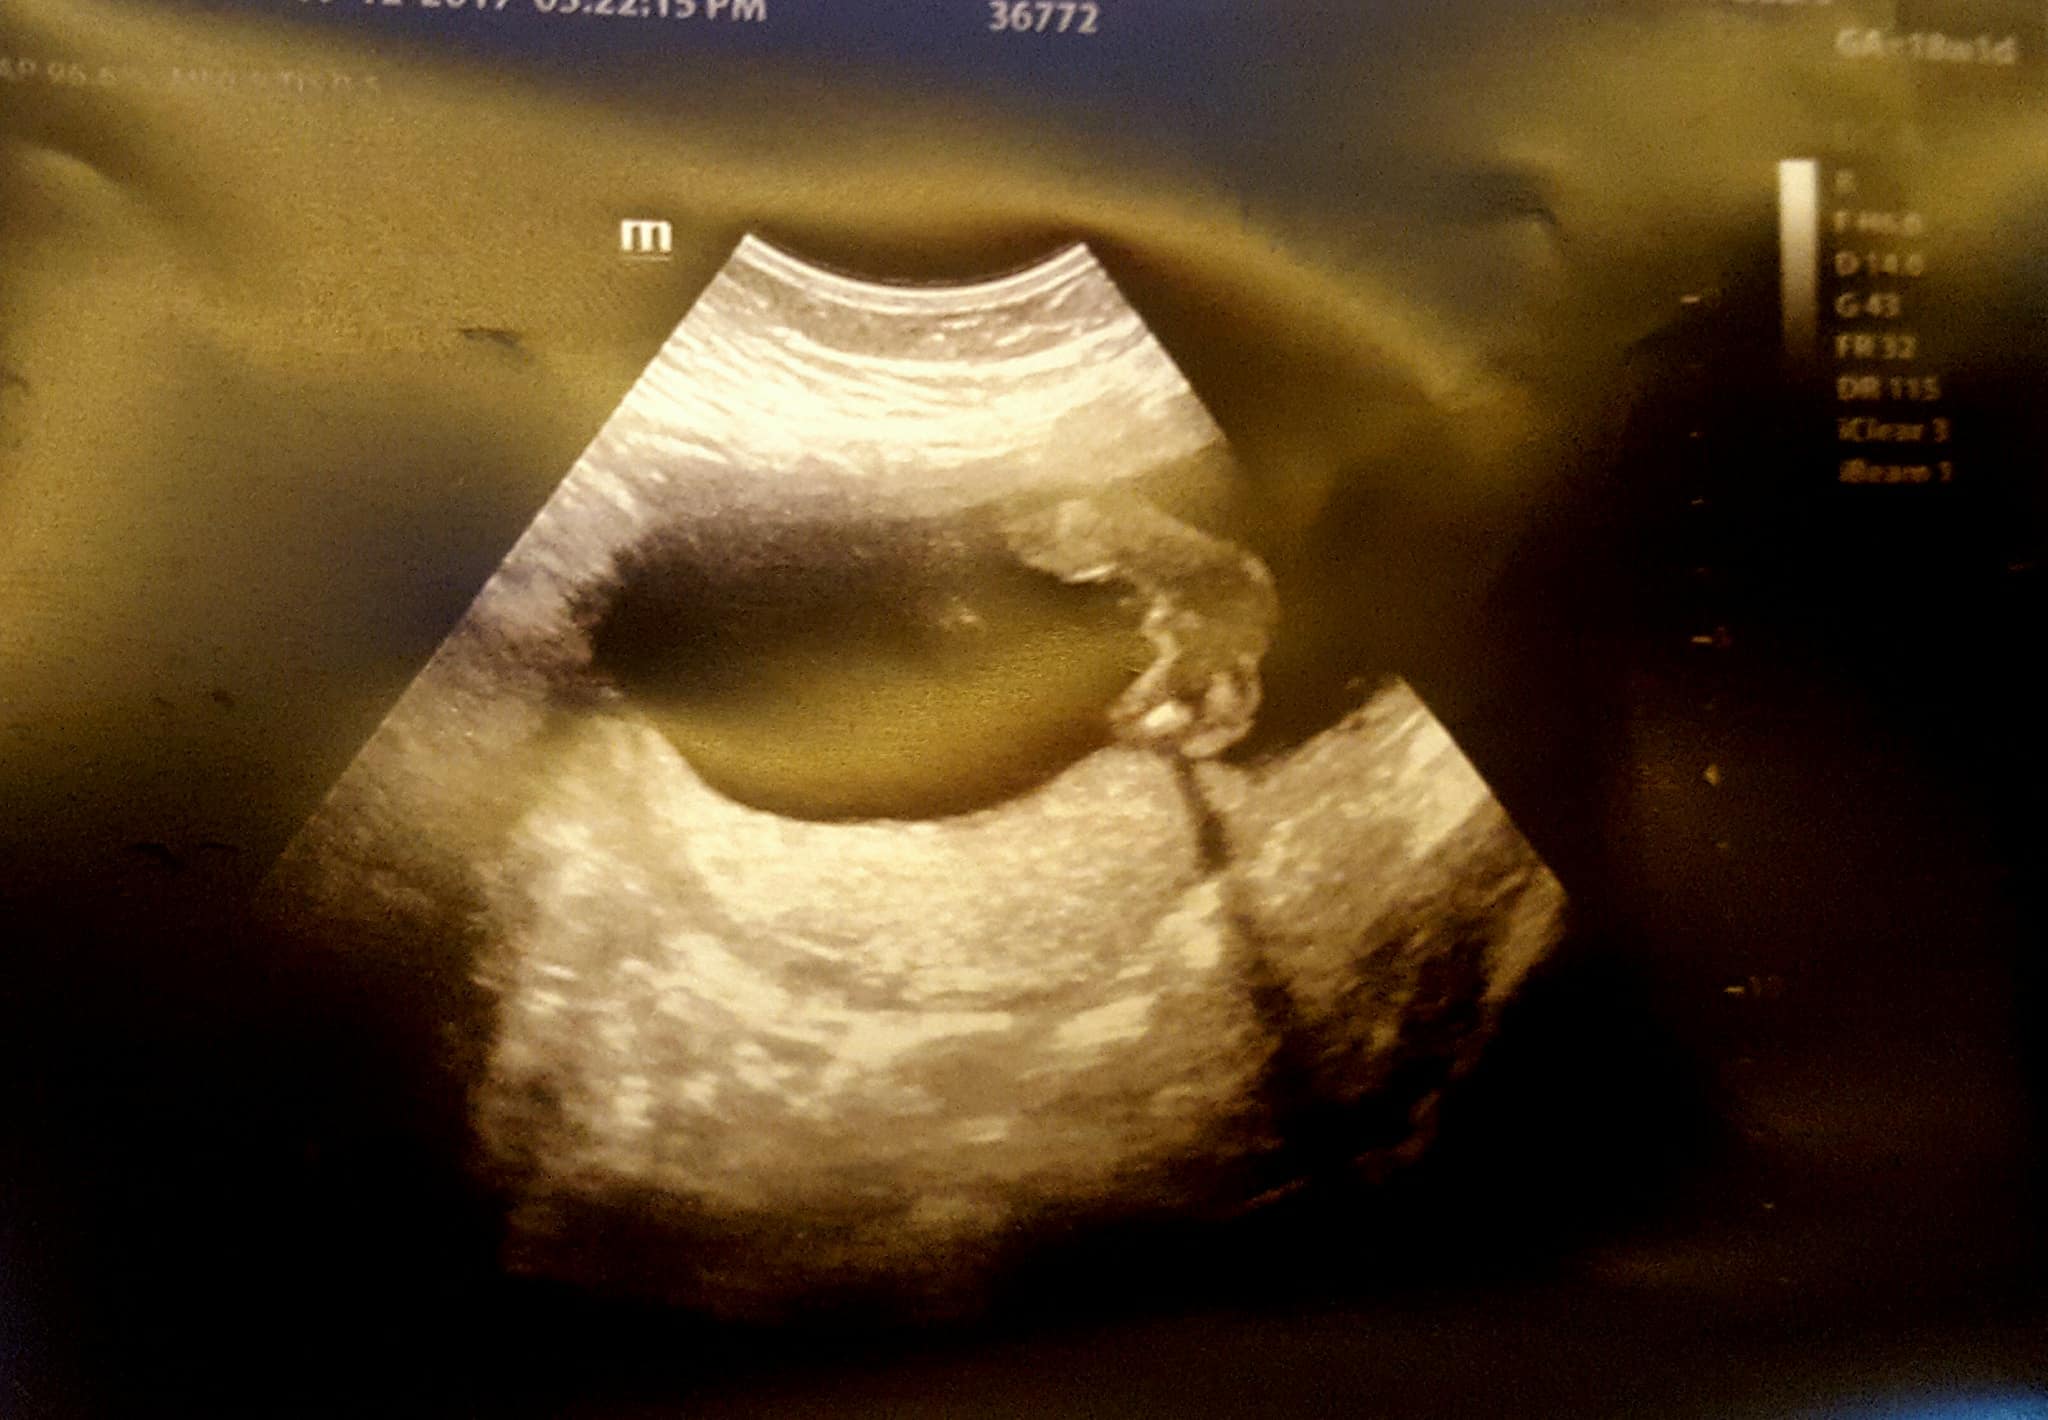

Here is my 18weeks scan. 1 picture looks boyish and 1 girlish :( Both are same day picture. Its confusing. I will have my Gender scan in 2 weeks. Any thoughts?

Attachment 38471

Top pic, BOY. The second pic is so far away that it's not a good shot of his goods but it still looks boyish to me. Didn't you have a blood test done to determine gender? I would believe that. Congrats on your BOY!!!

Top pic is obvious boy, the second pic is botched and just a bad pic. The techs can move their focus in or out and they just didn't capture the goods, that's all. :)